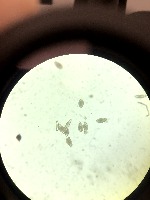

Water Quality Monitoring: Utilizing the Schisto computer vision model to analyze water samples under a microscope, helping in the identification and estimation of worm populations, thus assisting in water quality assessment, and detecting potential threats to public health or aquatic ecosystems.

Parasitology Research: Assisting researchers and medical professionals who study schistosomiasis (a parasitic disease caused by Schistosoma worms) by automatically identifying and classifying different life stages of the parasites, streamlining the analysis process, and supporting their research.

Disease Surveillance and Control: Implementing the Schisto model in mobile laboratories or fieldwork to monitor for the presence and distribution of Schistosoma worms, enabling effective surveillance and rapid response in managing potential disease outbreaks or implementing control measures.

Education and Training: Using the Schisto computer vision model as a educational tool in universities, research institutions, or training programs, providing students and professionals with an innovative way to develop their skills in microscopy and parasite identification, while reinforcing their knowledge of Schistosoma worms and associated diseases.

Pharmaceutical and Treatment Development: Assisting pharmaceutical companies and medical professionals in the development of new pharmacological treatments or vaccines targeting Schistosoma worms, by providing rapid and accurate identification of parasite life stages, supporting high-throughput screening of potential drug candidates, and enabling efficient monitoring of treatment outcomes.